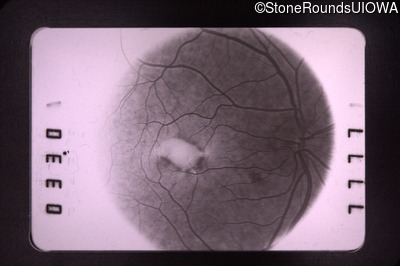

Fundus Photography - Left - 20/30 +1

Exemplar